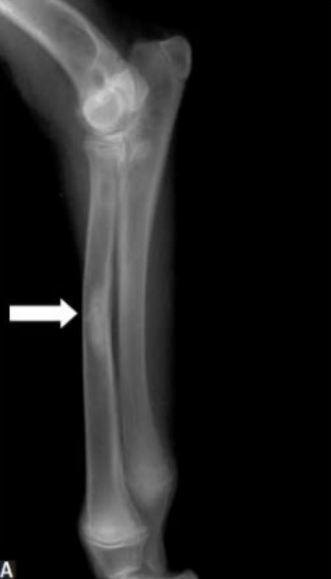

- 범골염 증상 (비교적 명확)

- 범골염 증상

- 범골염

- trabecular pattern

- 겉질과 골수관의 대비가 감소. 구별이 잘 되지 않아 경계가 흐릿